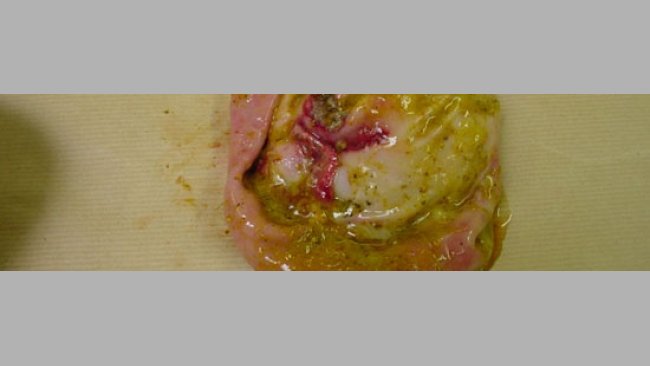

Con los análisis en la mano, se visita de nuevo la explotación para atender dos muertes más, pero esta vez de dos lechones, uno de ellos con 5 semanas de vida, y otro con una semana de entrada en cebo. Ambos mueren en el mismo momento, y cuando se observan los cadáveres, el animal mayor presenta también una coloración abdominal intensa oscura, así como parte de las orejas. El pequeño muestra una pequeña zona coloreada, pero presenta también un mayor grado de timpanización.

En la necropsia no se aprecia ninguna otra característica específica a las ya comentadas para la cerda reproductora, con la salvedad de la presencia de una mayor cantidad de gas, sin corresponder con los problemas de clostridiosis agudos que se conocían y de que ambos lechones tenían también parte del pulmón afectado de micoplasmosis, sin estar afectada la pleura.